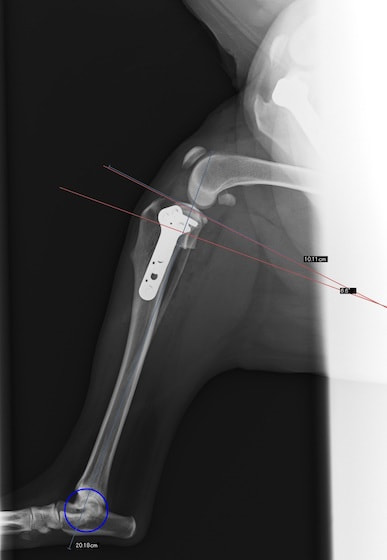

前十字靱帯断裂症例(2025/02/06)

HPの外科の前十字靱帯断裂のページに、犬のTPLO(脛骨高平部水平化骨切り術)手術を行った症例を追加致しました。大腿骨と脛骨を繋ぐ靱帯の一つである前十字靱帯が断裂すると、膝の関節が不安定となり関節炎が進行します。また膝関節内のクッションの役割を果たしている半月板にもダメージが加わり、痛みを生じて正常な歩行が出来なくなります。治療法としては術後の機能回復の早さから、近年ではTPLO法(脛骨の一部を円形に切り、角度を調整し膝関節を安定化させる手術)が多く選択されています。前十字靭帯断裂は中高齢犬によく見られる病気であり、膝蓋骨脱臼に併発することもあります。気になる症状がある場合はお早めにご相談下さい。

獣医師 臼井

症例報告(2024/08/27)

外科の前十字靱帯断裂のページに、犬のTPLO(脛骨高平部水平化骨切り術)手術を行った症例を追加致しました。大腿骨と脛骨を繋ぐ靱帯の一つである前十字靱帯が断裂すると膝の関節が不安定となり関節炎が進行します。また、膝関節においてクッションの役割を果たしている半月板にもダメージが加わり、痛みを生じて正常な歩行が出来なくなります。治療として多くの場合手術が選択されますが、術後の回復の早さなどから近年ではTPLO法(脛骨の一部を切り角度を調整し膝関節を安定化させる手術)が多く選択されています。

獣医師 白石

犬のTPLO(脛骨高平部水平化骨切り術)手術(2024/08/07)

外科の前十字靱帯断裂のページに、犬のTPLO(脛骨高平部水平化骨切り術)手術を行った症例を追加致しました。大腿骨と脛骨を繋ぐ靱帯の一つである前十字靱帯は、断裂すると膝の関節が不安定となり関節炎が進行し、またクッションの役割を果たしている半月板にもダメージが加わることで、痛みを生じて正常な歩行が出来なくなります。治療として多くの場合手術が選択されますが、術後の回復の早さなどから近年ではTPLO法(脛骨の一部を切り角度を調整し膝関節を安定化させる手術)が多く選択されています。